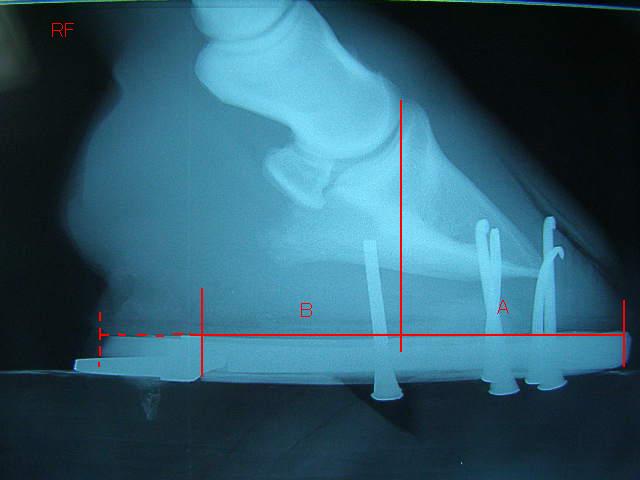

装蹄に先立ち、治療開始3ヶ月後のレントゲンを撮りました。

昨年9月のものと比較してみます。

9月の左前肢

今回の左前肢

ラメラーウェッジがだいぶ取り除かれ、蹄が蹄壁にきちんとくっついて生えてきているのが確認できてホッとしました。